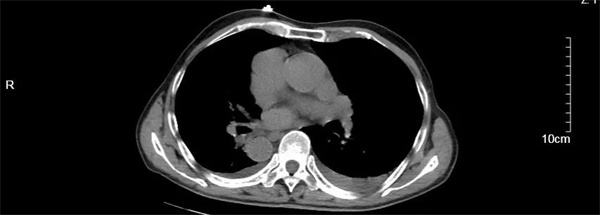

汪大爷因“反复胸闷气喘1周伴头昏”在当地卫生院就诊,心电图检查显示高度-III度房室传导阻滞(心室率40次/分)和镜像右位心心电图。由医共体转诊中心转至我院进一步诊治。入院后,行24小时动态心电图和心脏彩超检查发现,患者不仅患有II度房室传导阻滞,呈2:1下传(最慢心率35次),交界性逸搏伴干扰性房室分离。彩超更是发现汪大爷还是一位罕见的镜面右位心,其心脏及腹腔内脏器官位置与正常人完全相反,如同正常脏器的 “镜中像”,这种先天性畸形的发生几率约为1/100万。